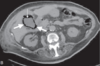

What is the diagnosis? Describe the findings

Emphysematous cholecystitis CT scan demonstrating a luminal air-liquid level and air within the wall of the gallbladder.